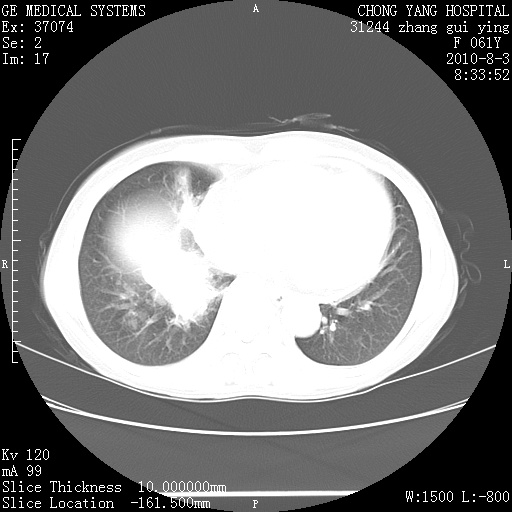

标题: CT28314:F61Y胸部增强,发热咳嗽一周入院,后面的为一周前平

1、支持考虑右侧中央型肺癌伴右肺中叶节段性不张及下叶支气管黏液痰栓    2、左肺上叶舌段感染。

支持右下肺中央型肺癌并左上肺感染.

双肺感染性病变,不除外合并结核感染。

确切的说:1:右肺下叶中心型肺癌侵及中叶支气管并中叶不张,纵膈淋巴结转移。2:左肺舌叶炎症。3:右侧胸腔少量积液

1:右肺下叶中心型肺癌侵及中叶支气管并中叶不张,纵膈淋巴结转移。2:左肺舌叶炎症。3:右侧胸腔少量积液。支持!